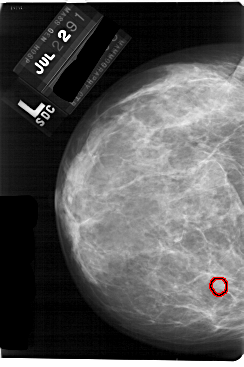

A_1757_1.LEFT_CC

LEFT_CC LINES 5491 PIXELS_PER_LINE 3646 BITS_PER_PIXEL 12 RESOLUTION 43.5 OVERLAY

FILE: A_1757_1.LEFT_CC.OVERLAY

TOTAL_ABNORMALITIES 1

ABNORMALITY 1

LESION_TYPE MASS SHAPE ROUND MARGINS OBSCURED

ASSESSMENT 3

SUBTLETY 3

PATHOLOGY BENIGN

TOTAL_OUTLINES 1

BOUNDARY